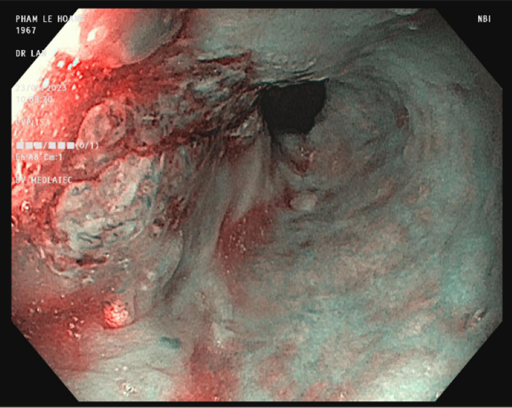

Đến Bệnh viện Đa khoa MEDLATEC thăm khám với tình trạng nuốt nghẹn, ăn uống nghẹn, sặc thức ăn lỏng, ợ hơi, ợ chua, người đàn ông 70 tuổi phát hiện ung thư thực quản nghi ngờ di căn phổi. Đặc biệt, trước đây 10 năm ông đã từng phải phẫu thuật cắt 3/4 dạ dày vì ung thư.